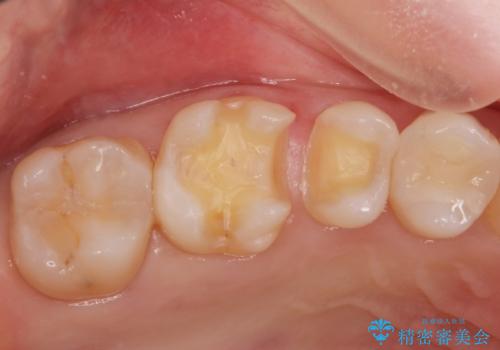

拡大鏡下で詰め物を外しう蝕がないことを確認して、e-maxインレーにて治療しました。

セラミックの詰め物は歯質とピッタリ適合して虫歯の再発率が低いです。

白い詰め物が入り大変満足して頂けました。